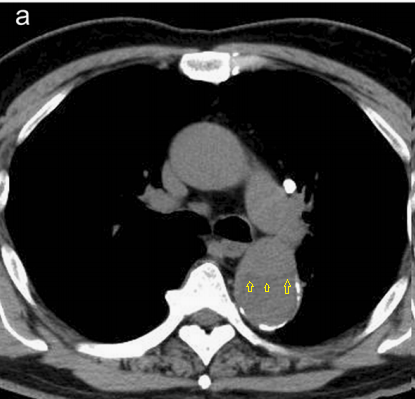

病例7

你看,我家的CT这么模糊,平扫怎么看主动脉夹层?

图18

不着急!仔细看,血管里面的“血液”居然钙化了!这叫血管钙化内移,要警惕主动脉夹层!有研究发现,血管钙化内移诊断动脉夹层的特异性高达90%。

图19

赶紧做个增强CT!主动脉裂开了!

图20